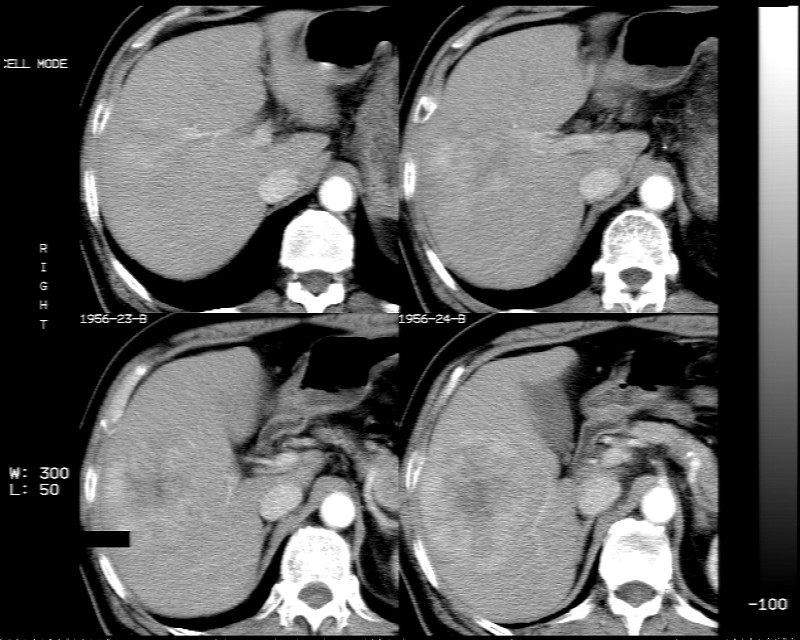

男 73岁 b超检肝右叶占位病变,afp阴性. 随访中.

平扫示:肝右后叶下段内见类圆形略低密度占位病灶,边界尚清楚,最大径约为102×71mm,ct值31~41hu。

动态增强扫描示:动脉期病灶显著不均性强化,病灶强化密度高于肝实质;平衡期病灶呈等密度;延迟扫描病灶密度略低于肝实质;三期均见占位病灶内有裂隙状无强化影。肝内胆管无扩张,腹膜后未见肿大淋巴结。

拟诊:肝右后叶下段内占位性病变,考虑为肝结节样增生。

建议进一步检查(mri/或穿刺活检),不排外肝ca。